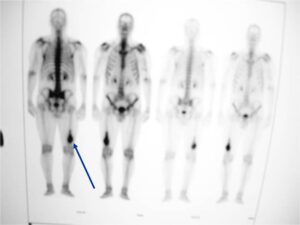

- Metastasizes primarily to lungs

- Also bones and other organs

- Predominantly in lungs